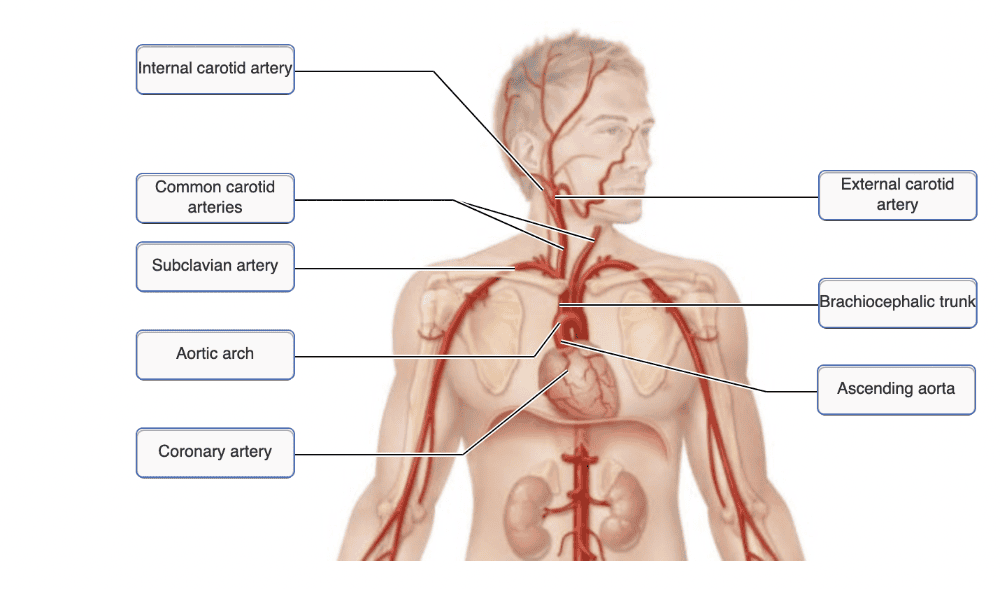

A thrombus (blood clot) in the first branch of the arch of the aorta would affect the flow of blood to the ________.

- left upper arm

- left side of the head and neck

- right side of the head and neck and right upper arm

- myocardium of the heart

right side of the head and neck and right upper arm

From what artery does the right common carotid artery arise?

- brachiocephalic trunk

- aortic arch

- external carotid artery

- internal carotid artery

brachiocephalic trunk

Ex.

The brachiocephalic trunk is found only on the right side of the body, and it splits to form the right common carotid artery and the right subclavian artery. These two arteries arise independently from the aorta on the left side of the body.